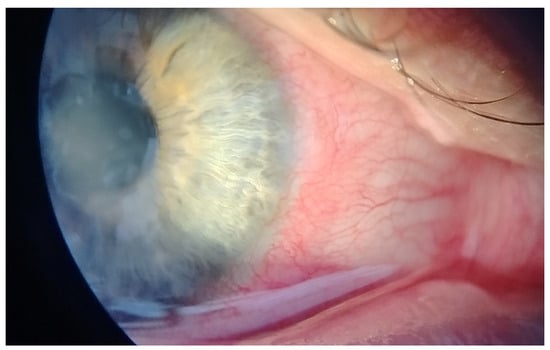

This case report describes a 35-year-old female who presented with redness, pain, tearing, photophobia, and vision loss in her right eye, beginning in mid-September 2024. The patient was a soft contact lens wearer due to myopia of −6.00 DS and reported showering and occasionally sleeping while wearing her contact lenses. She was initially treated for five days with topical corticosteroids and antibiotics by her primary care doctor, with no improvement, after which she was referred to an ophthalmologist. At her initial presentation in October 2024 at the University Hospital Centre Zagreb, the best-corrected visual acuity (BCVA) of the right eye was 0.4 logMAR. Slit-lamp examination revealed pronounced perilimbal injection (Figure 1), two fluorescein-negative stromal infiltrates at the 4 and 8 o’clock positions, and diffusely reduced corneal transparency with a centrally located ring-shaped infiltrate (Figure 2). Perineural infiltrates were also observed (Figure 3).

Figure 2. Stromal infiltrate (red arrow) and ring-shaped infiltrate (yellow arrow).